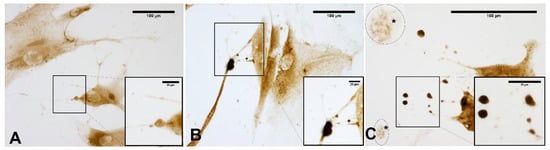

2.7. Staining Protocols

2.8. Immunocytochemistry to Detect HABP (Hyaluronic Acid Binding Protein)

2.9. Immunocytochemistry to Detect Collagen Type I and III